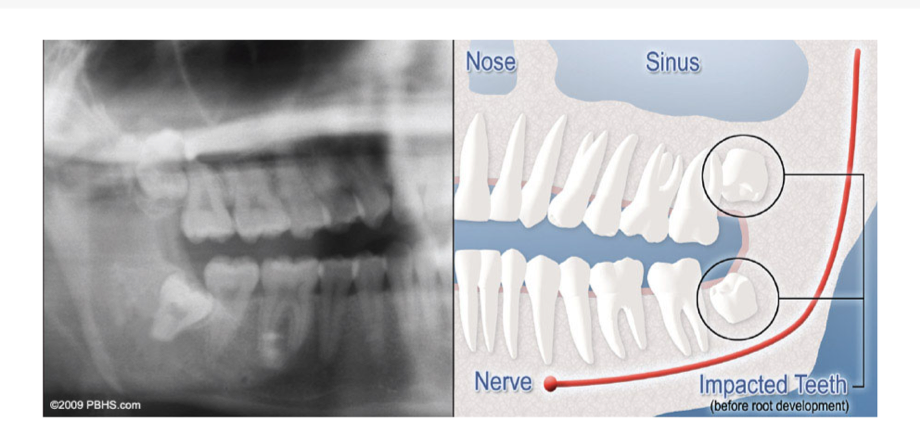

When a tooth doesn’t fully grow in, it’s impacted – usually unable to break through the gums because there isn’t enough room.

WHAT IS AN IMPACTED TOOTH?

Although most people develop and grow 32 permanent adult teeth, many times their jaws are too small to accommodate the four wisdom teeth. When inadequate space prevents the teeth from erupting they are called impacted. This indicates their inability to erupt into the proper position for chewing and cleaning

We will need to see you for a consultation to determine if you will benefit from wisdom tooth removal. A special x-ray of your mouth and jaws (panorex) will be taken to determine if your wisdom teeth are impacted, if there is room for them to erupt, and how difficult it will be to have them removed.